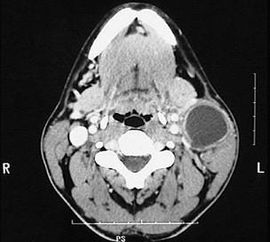

先天性第一鰓裂囊腫廈瘺管臨床少見,易誤診、誤治。影像學檢查是術(shù)前確診的重要依據(jù);充分的術(shù)前準備和合理的手術(shù)方案是該病治愈的關(guān)鍵,完整切除囊腫度瘺管是避免復(fù)發(fā)的重要措施。